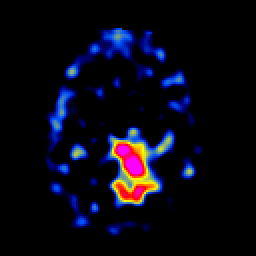

SPECT TL Study #5 -- Slice #39

[Home][Help][Clinical][Tour 1][Tour 2][Tour 3] Slice 39